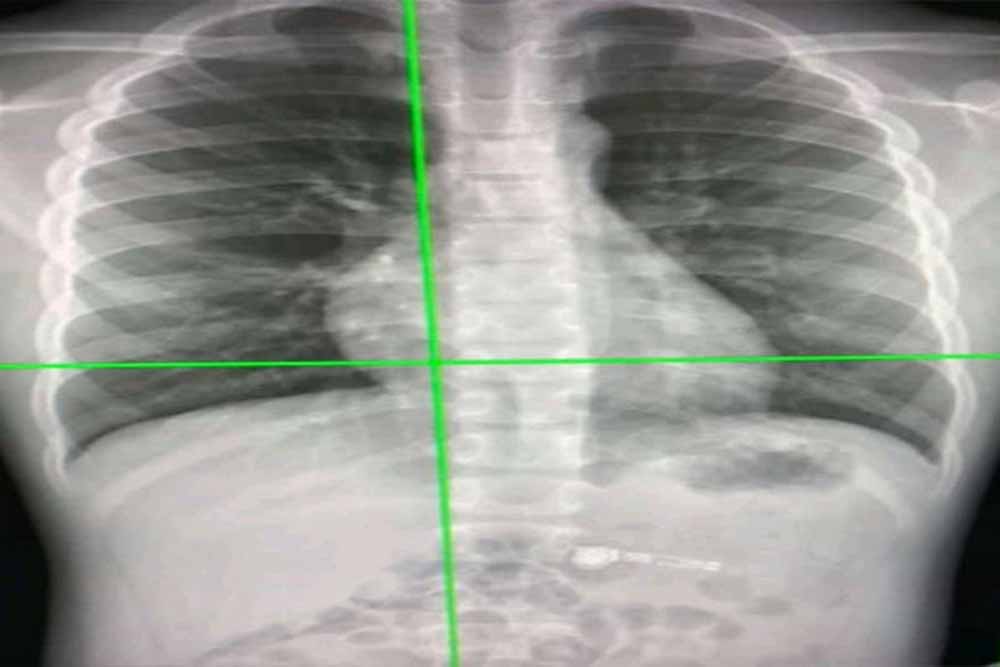

ऑस्ट्रेलियाई शोधकर्ताओं ने एक आर्टिफिशियल इंटेलिजेंस सिस्टम विकसित किया है जो छाती के एक्स-रे से कोविड-19 के संक्रमण को 98 प्रतिशत से अधिक की सटीकता से पता लगा सकता है। यह वर्तमान में उपयोग किए जाने वाले आरटी-पीसीआर परीक्षण की तुलना में अधिक फायदेमंद हो सकता है।

उन्होंने कहा, "नया एआई सिस्टम उन देशों में विशेष रूप से फायदेमंद हो सकता है जहां उच्च स्तर पर कोविड-19 अनुभव हो रहा है, जहां रेडियोलॉजिस्ट की कमी है। चेस्ट एक्स-रे पोर्टेबल हैं, व्यापक रूप से उपलब्ध हैं और सीटी स्कैन की तुलना में कम जोखिम प्रदान करते हैं।" कोविड-19 के सामान्य लक्षणों में बुखार, खांसी, सांस लेने में कठिनाई और गले में खराश शामिल हैं, लेकिन कोविड-19 को फ्लू और अन्य प्रकार के निमोनिया से अलग करना मुश्किल हो सकता है।

साइंटिफिक रिपोर्ट्स जर्नल में प्रकाशित एक पेपर में विस्तार से बताया गया है कि नया एआई सिस्टम कस्टम कन्वोल्यूशनल न्यूरल नेटवर्क नामक एक गहन शिक्षण आधारित एल्गोरिदम का उपयोग करता है जो एक्स-रे फोटोज में कोविड -19 मामलों, सामान्य मामलों और निमोनिया के बीच जल्दी और सटीक रूप से अंतर करने में सक्षम है। प्रोफेसर गैंडोमी ने कहा, "डीप लर्निंग एक एंड-टू-एंड समाधान प्रदान करता है, जो बायोमार्कर को मैन्युअल रूप से खोजने की आवश्यकता को समाप्त करता है। कस्टम-सीएनएन मॉडल पता लगाने की प्रक्रिया को सुव्यवस्थित करता है, जिससे कोविड-19 का तेज और अधिक सटीक निदान मिलता है।"